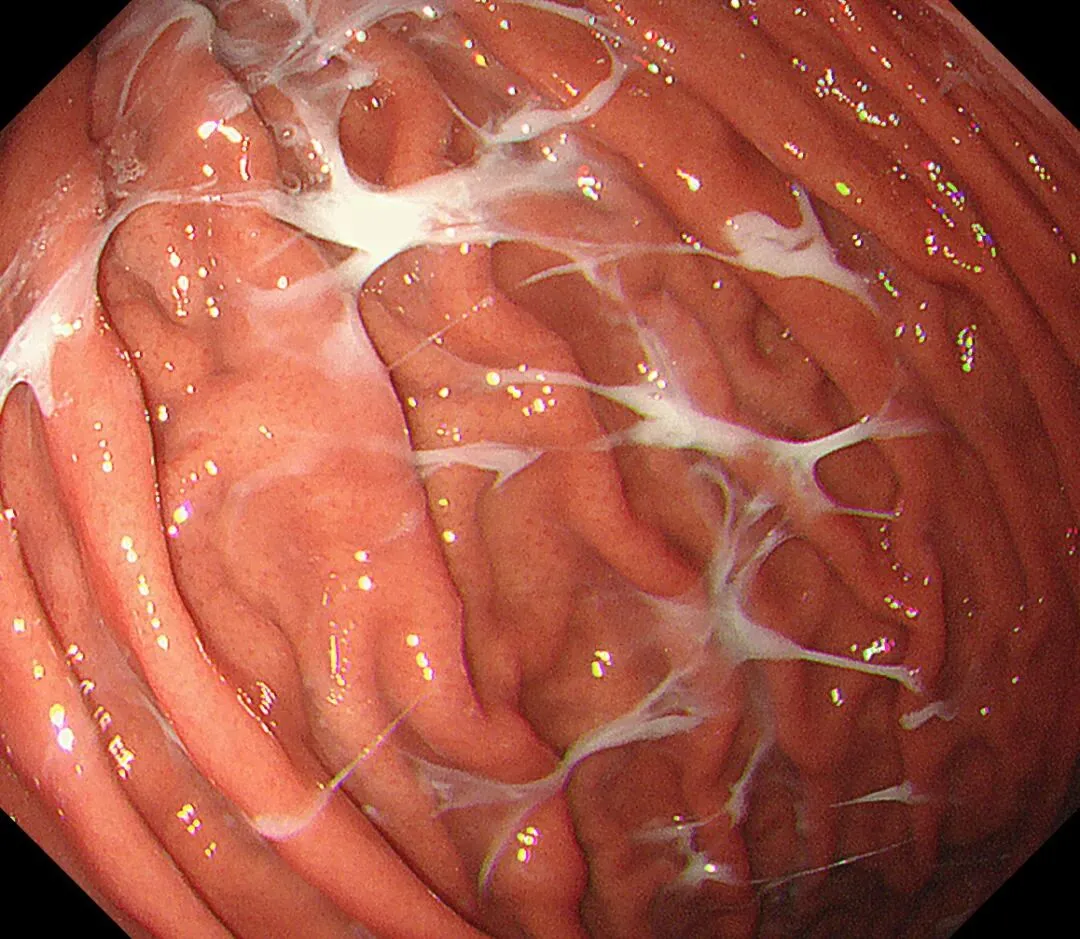

蛛网状黏液(web-like mucus):以胃底、胃体大弯为中心,有时可见白色透明、水洗难以去除的黏液附着,因外观与蜘蛛网相似而命名,多见于口服钾离子竞争性酸阻滞剂(P-CAB)患者,可能是因为其强效、持续抑酸作用所致,具体机制尚需进一步研究明确。

蛛网状黏液case1,服用P-CAB药物(具体服用时长不详)👇